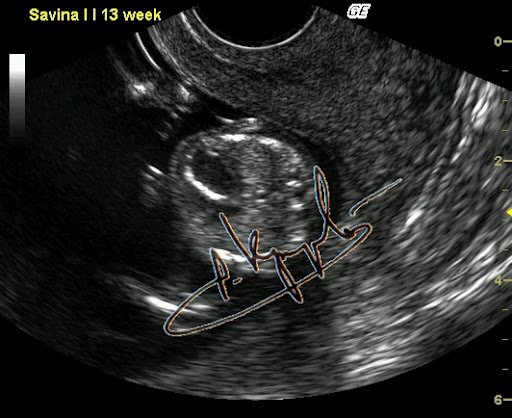

Фиброэластоз эндокарда. Диагностика на ранних сроках возможна.

Вот как быть? Вроде обещал нескольким человечкам рассказать про внутриутробный фак, но совершенно не уверен что получится что-то путнее. Хотя чем черт не шутит. Попробую. Было это буквально на днях, в четверг. Но лучше издалека начать. С именем Настя у меня по жизни непременно связан какой-то налёт чудесатости. Ну есть что-то такое... Что-то буквально на кончике не пойми чего. Как модно говорить "флёр @панутости". То, что даже издалека отличает любую Настю от носительниц других имен. Или, перефразируя вышесказанное, - нормальных Насть я в своей жизни пока не встречал. Это в качестве предисловия, хотя некоторые и осуждают любые эпиграфы. А кто сказал эпиграф? Я сказал - предисловие. Чуете разницу? Нет? Дело ваше. Полумрак кабинета. Беременность 24 недели. И Ваш покорный слуга, мучающий подслеповатые (уже весьма-весьма, увы) глаза перед экраном, согнувшись над животиком. УЗИ делаю. Сердце плода исследую (эхокардиография называется). Когда-то давно я эту методику отработал до совершенства. Ну то да сё, кровоток через клапаны, время изгнания, время релаксации и прочая хитромудрая мутотень. Тут Настя и говорит: - Ну что, показывает? Кто там у нас? (Настя - это беременная) - Какой пол? А разве не говорил на прошлом УЗИ? - Нет, не было видно. Ну это часто бывает. Вот втемяшится что-то ребятенку в животике и так упрется рогом в плаценту, то можно и до самых родов не узнать. Вот всеми возможными способами будет прятаться. То руками закрывать, то пуповину наматывать, то ноги сжимать. Ну бывает, поэтому особо не придал значения. Сердце закончил обследовать, - все нормально. И слава Богу. - Хорошо, говорю, - сейчас посмотрим кто-там прячется. Начал пытаться разглядывать. И так и сяк, короче и руку себе вывернул и глаза сломал. Потом на пару секунд плод ноги разжал и рукой, которой свою письку прикрывал, показал мне... натуральный фак. Секунды три подержал средний палец мне перед глазами и опять руки в промежность и ноги сжал. Я не выдержал и расхохотался. Мамашке говорю: - никогда мне еще за 25 лет с экрана плоды фак не показывали. Тут уже мамашка в хохот. Я весь в непонятках. А она мне: - Доктор, так в прошлый раз Вы тоже рассмотреть не могли, я три раза на кушетку ложилась и вставала. Но в тот раз ребенок вам... козу показывал. И правда. Вспомнил таки эту Настю. Кинулся искать в базе данных. И действительно - так и записано: Бурум-бурум Анастасия Паповна, Бер 18-19 нед, КЗ, ХЗ(показывала козу). И вот если бы мне кто рассказал, я бы не поверил. И главное - это оказалась девочка!!! Представляете, что за хулиганка растет? Кстати, у этой истории еще и продолжение есть. Но не сегодня.